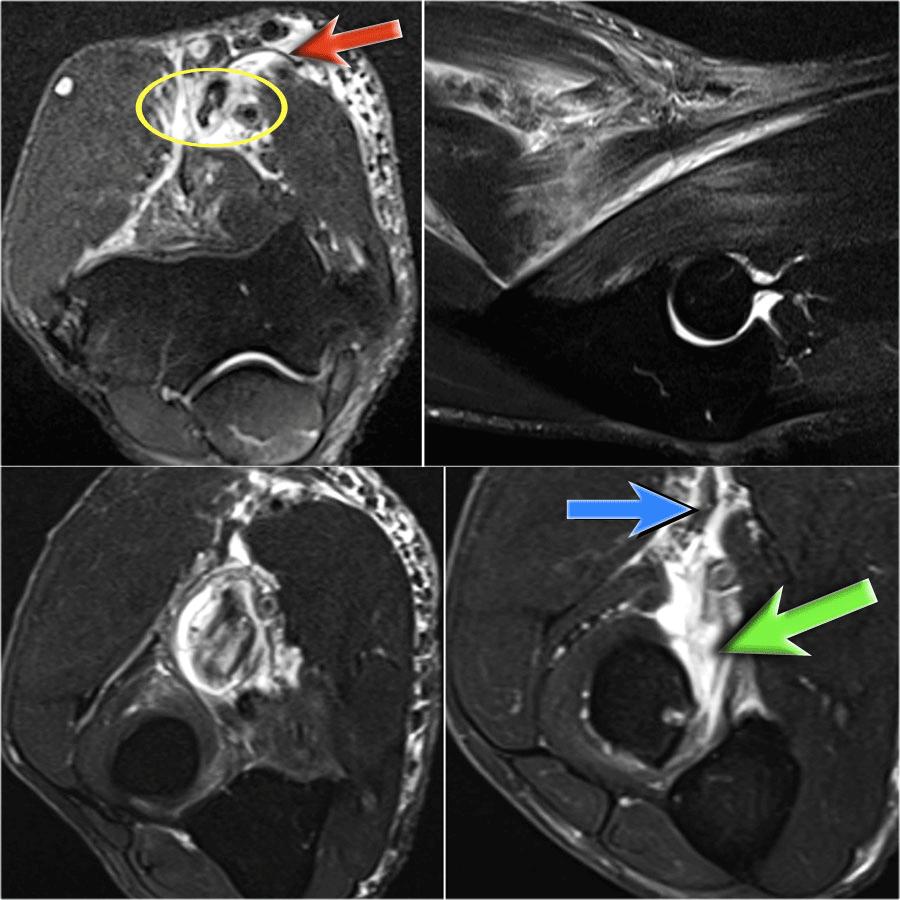

Tear of distal biceps tendon

Có một vết rách hoàn toàn, vì nếu chúng ta theo dõi gân đến tận củ quay, chúng ta có thể thấy rằng gân không bám vào đó (mũi tên xanh lá).

Chỉ có dịch.

Lý do tại sao gân không bị co rút là vì cân cơ nhị đầu rộng – còn được gọi là lacertus fibrosus – vẫn còn nguyên vẹn (mũi tên đỏ).

Gân nhị đầu xa không chỉ bám vào lồi củ xương quay, mà còn thông qua lacertus fibrosus bám vào cân cơ của khối cơ gấp-sấp ở phía trong cẳng tay.

Gân xa của cơ nhị đầu được khoanh tròn ở hình ảnh phía trên bên trái.

Khi cân cơ cũng bị rách, thì gân sẽ co rút lại và bạn sẽ thấy một khối phồng rõ ràng ở cánh tay do cơ nhị đầu bị co lại.